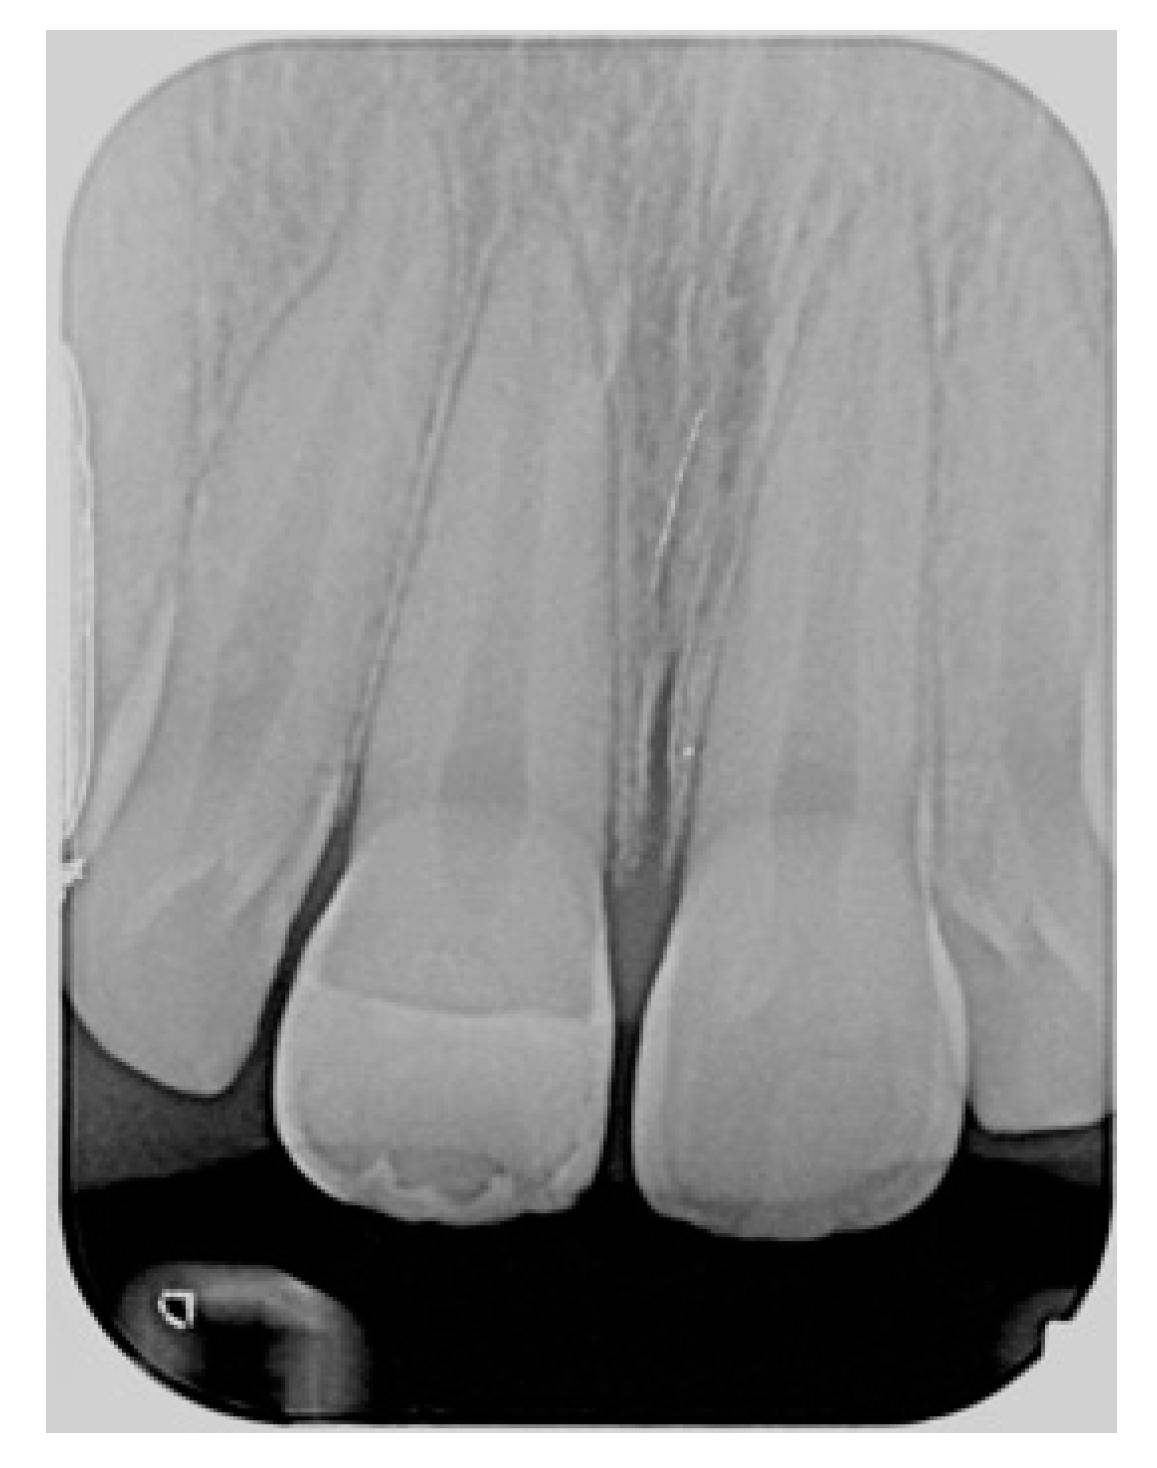

Figure 19.

Five years post-operative x-ray.

Finishing and polishing procedures were performed with a diamond bur (WL 268 014 Horico, Berlin, Germany), silicone points (Identoflex, Kerr, Bioggio, Switzerland) brushes (Jiffy Goat Air Brushes, Ultradent Products, South Jordan, UT, USA), and diamond pastes (Diamond Polish Mint, Ultradent Products, South Jordan, UT, USA) (Figure 13 and Figure 14). Satisfactory clinical and radiographic outcome was considered satisfactory at 3-months, 1-year, and 5-years post-operative (Figure 15, Figure 16, Figure 17, Figure 18 and Figure 19).